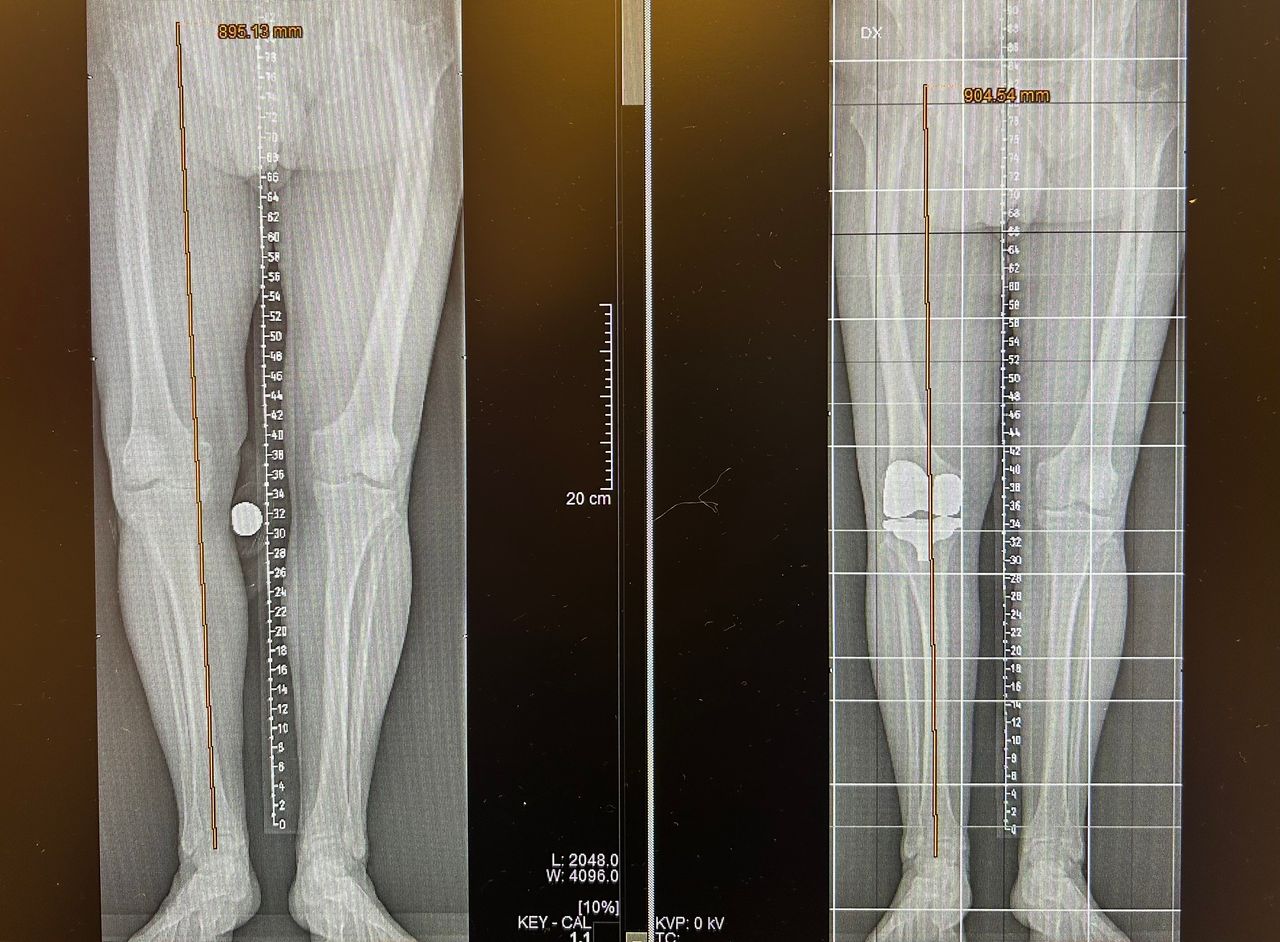

Per una maggiore completezza della visita è utile avere a dispozione almeno una Radiografia standard o Risonanza Magnetica recenti.